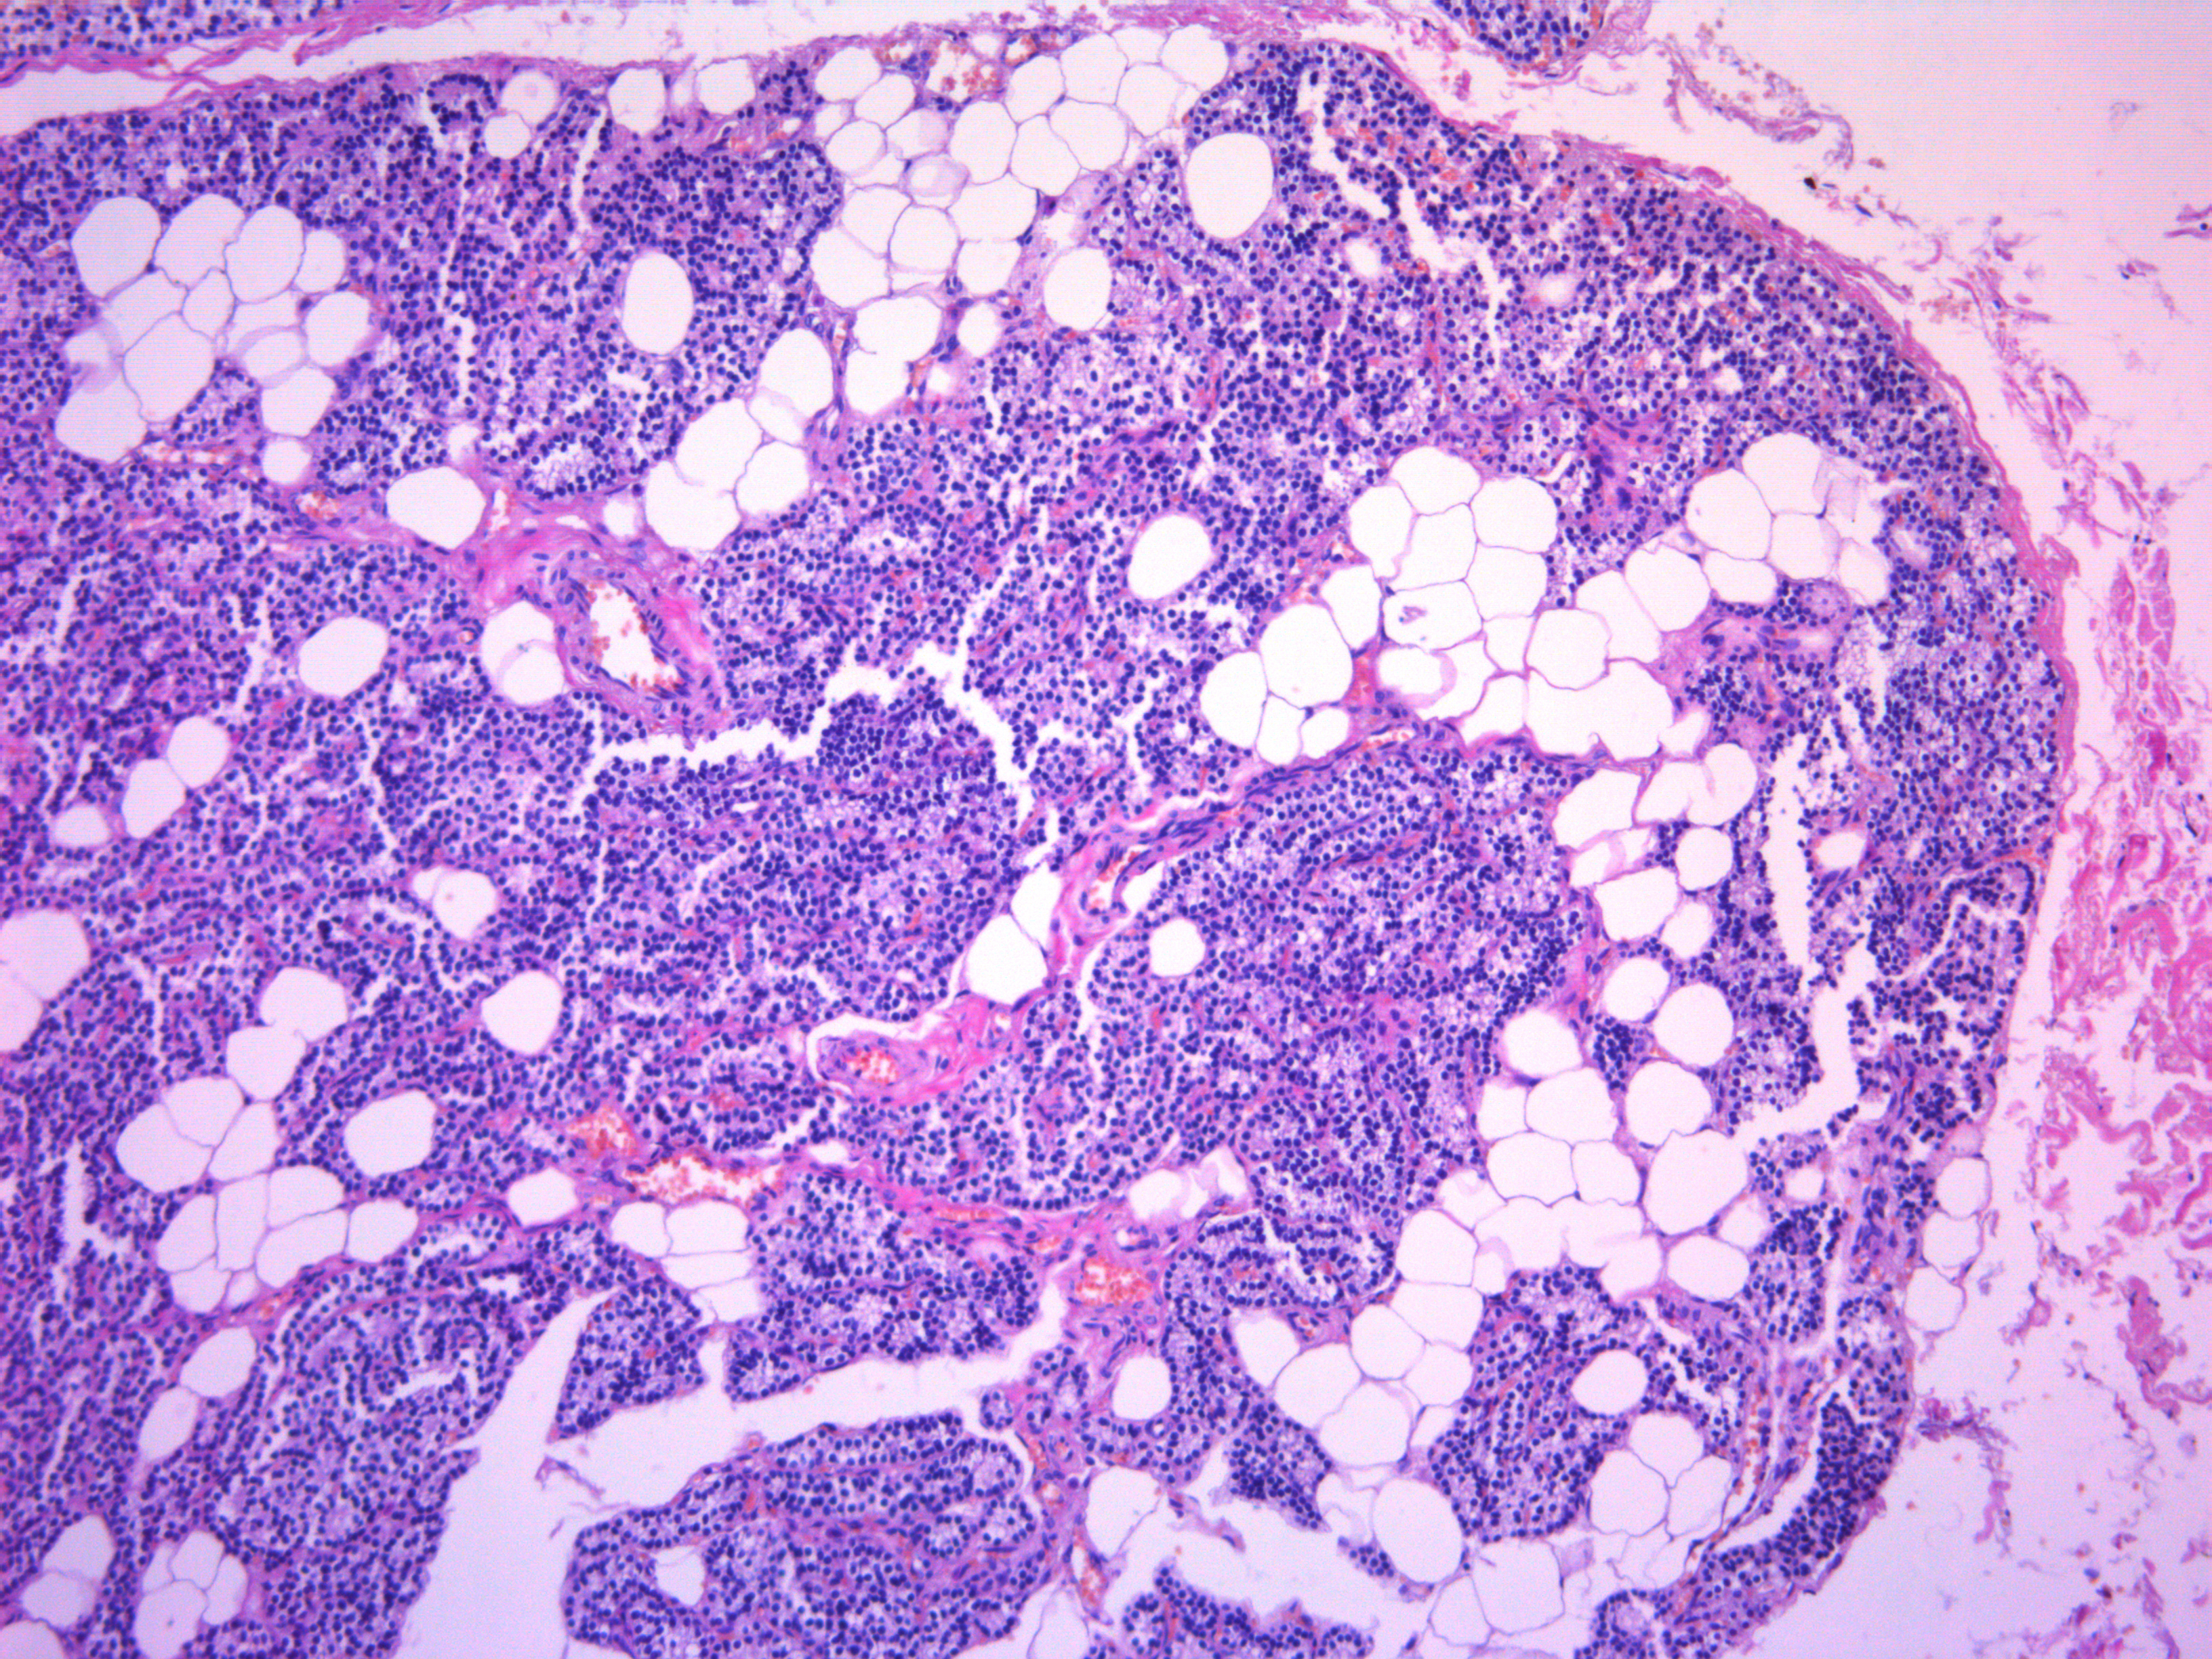

2. Рисунок 1Б | |

3. Рисунок 2 | |

1. Рисунок 1А | |